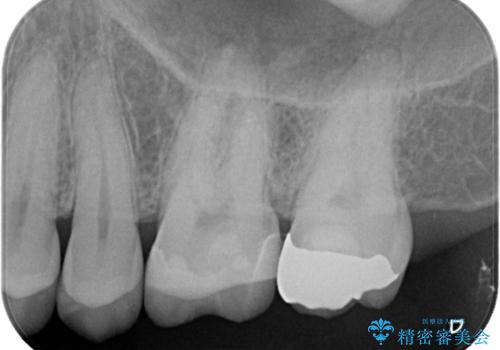

【セラミックインレー】歯科検診にて虫歯発見。

- 定期健診にて虫歯を見つけたためセラミックインレーにて修復しました。

綺麗に仕上がり患者さんも非常に満足されていました。

当院でのセラミックインレーはラバーダム防湿をして接着しております。